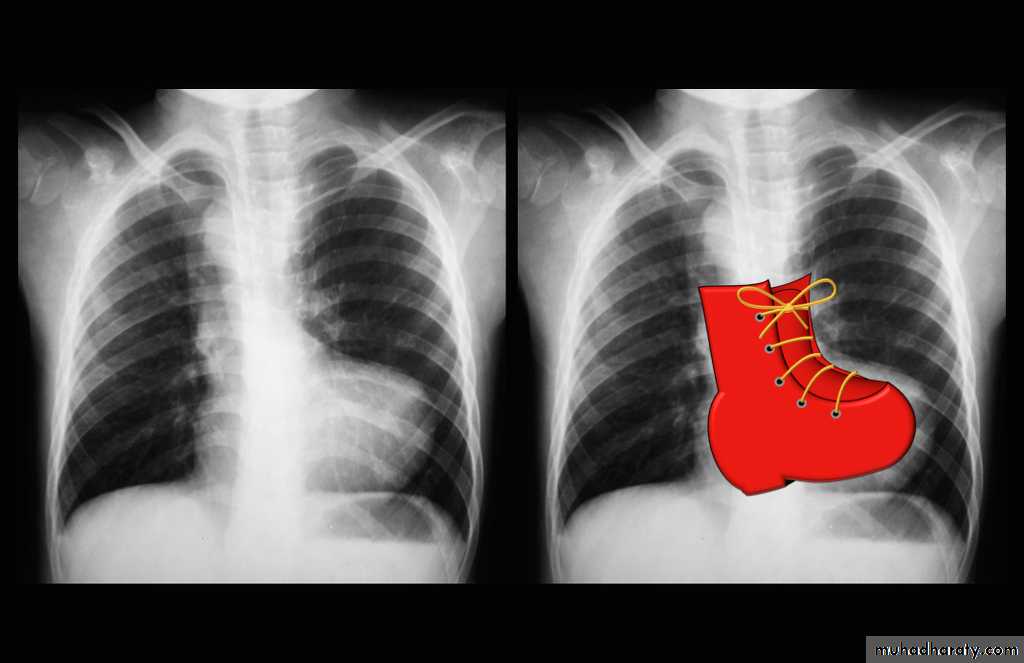

Chest X ray:

Right ventricular enlargementPulmonary bay (underdeveloped pulmonary artery)

The combination of these findings gives the “boot-shaped heart”